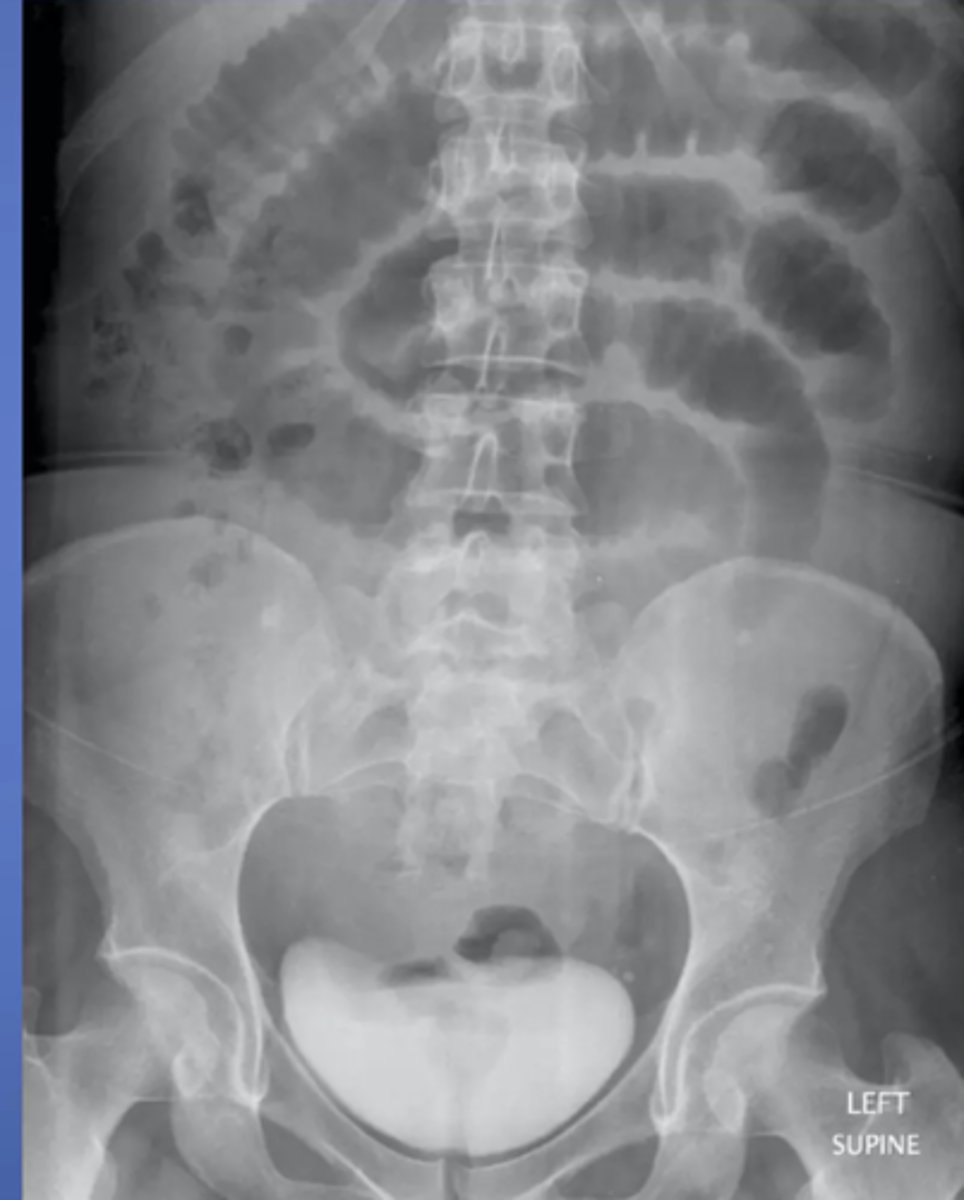

Large bowel obstruction

MC areas of LBO

cecum, hepatic/splenic flexures, sigmoid colon, upper portion of the rectum

_____ valve determines the radiographic appearance of LBOs

ileocecal

competent ileocecal valve (closed loop)

gas and feces can't reflux into small bowel, pressure builds up only in colon

incompetent ileocecal valve (open loop)

gas and fluid reflux backward into small bowel

MC cause of LBO?

tumor